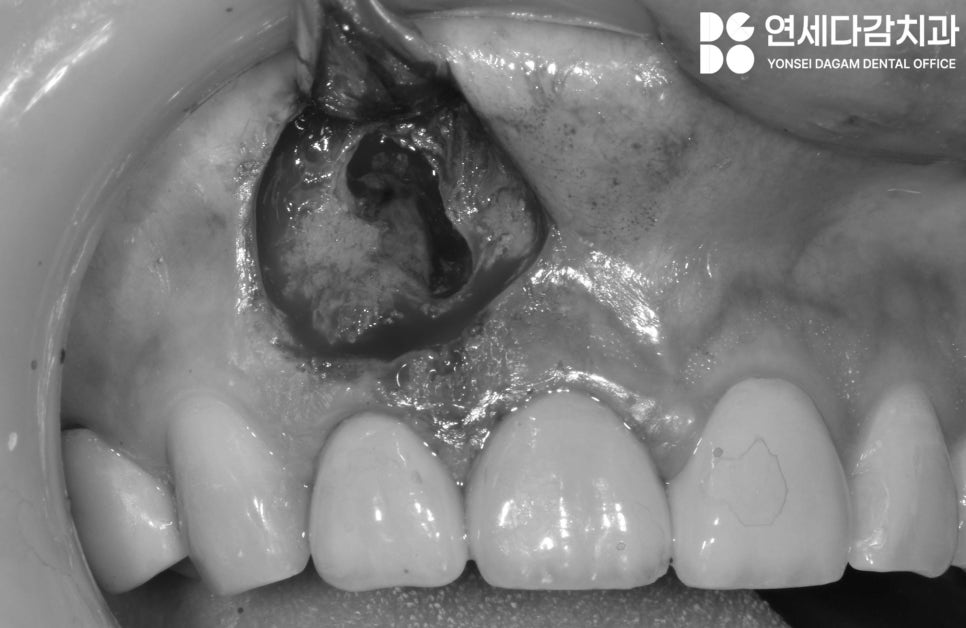

병소 부위의 육아조직과

감염된 조직을 깨끗이 제거합니다.

감염된 뿌리 부위를 절제한 뒤

끝부분을MTA(Mineral Trioxide Aggregate)와

같은 생체친화적 재료로 역충전합니다.

MTA는 뛰어난 밀폐성과

생체적합성을 가지고 있어,

근관 밀봉에 이상적입니다.

또한 습한 환경에서도 경화가 가능하며,

항균 효과가 있고

주변 조직의 치유를 촉진합니다.